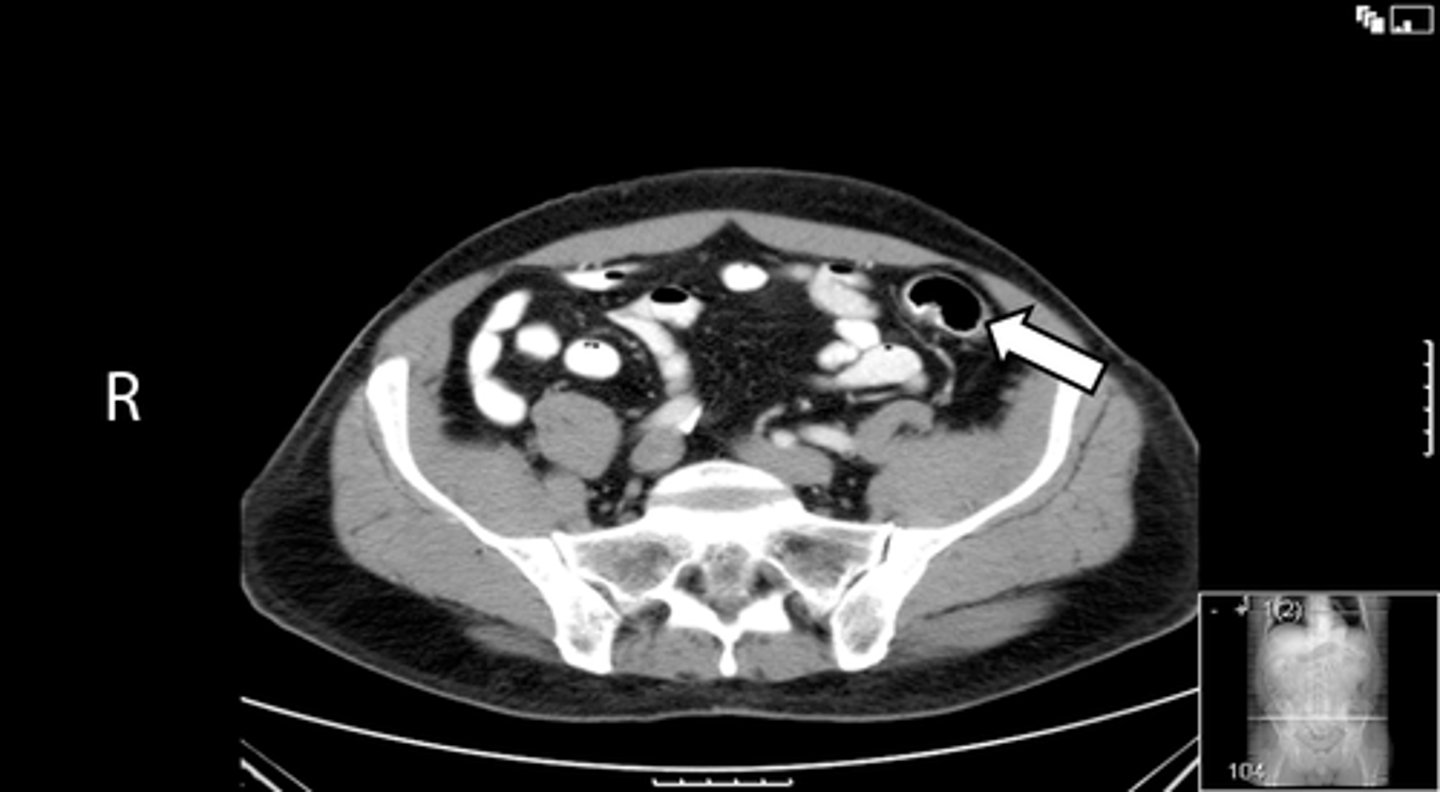

Axial bony pelvis CT

What is the image?

38

L acetabulum

What is indicated in the image?

<p>What is indicated in the image?</p>

New cards

L femoral head

40

L piriformis muscle

R femoral head

42

R piriformis muscle

R acetabulum (posterior part)

44

Sacrum